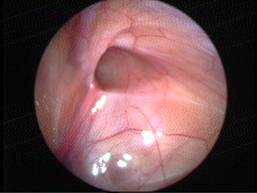

Can this operation be done laparoscopically?

Operation in hydrocele involves closing of the open passage through which the testis has come down. This can be done from outside as in open surgery or from inside by laparoscopy. With the help of laparoscopy we are able to look at the opposite side to see if the passage is open on that side as well. This can be closed at the same sitting if you wish to. Recovery from surgery, timing of surgery and discharge from hospital are the similar for open surgery and laparoscopic surgery.

However, it is important to note that an open passage does not always mean that your child will get a hydrocele or hernia on the opposite side. There is no harm in opting for a second surgery later if your child at all develops a hernia on the opposite side.

Laparoscopic repairs have a slightly higher chance of recurrence as compared to open surgery. You can discuss the pros and cons in details with your doctor when you come for consultation.